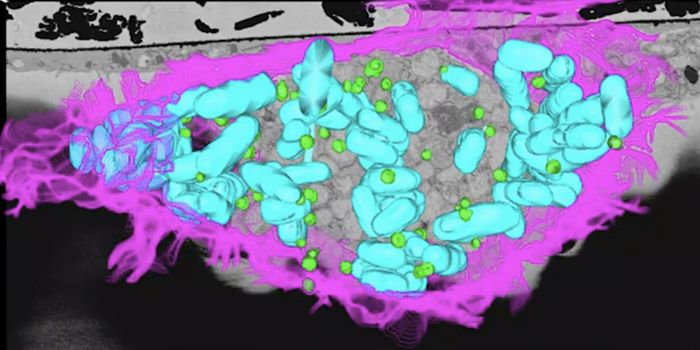

OCT 05, 2021ImmunologyMany of the deadly viruses that affect humans—including Ebola and HIV—have animal origins. These infectious ...